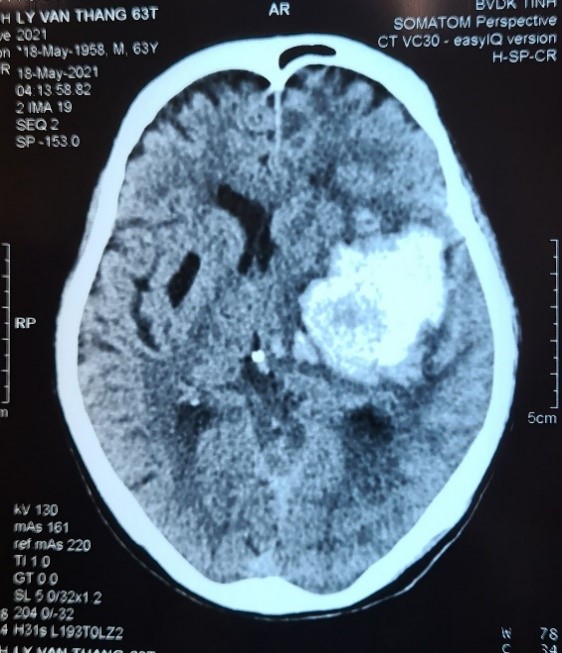

Bệnh nhân Lý Văn T. (63 tuổi) đột ngột xuất hiện tình trạng đau đầu, bất tỉnh được gia đình cấp cứu tại cơ sở rồi chuyển đến Bệnh viện Đa khoa tỉnh Hòa Bình. Lúc vào viện bệnh nhân trong tình trạng hôn mê Glassgow 9 điểm, thở khò khè, liệt nửa người phải, huyết áp 190/100mmHg. Kết quả chụp cắt lớp cho thấy hình ảnh chảy máu não vị trí nhân nền thái dương trái đè đẩy đường giữa nhiều, phù não xung quanh. Bệnh nhân đã được làm các xét nghiệm, hội chẩn cấp cứu các chuyên ngành Hồi sức cấp cứu, Ngoại Thần kinh với tình trạng xuất huyết não khối lượng lớn, chèn ép não nhiều cần phẫu thuật cấp cứu lấy máu tụ, cầm máu và giải áp não.

Hình ảnh chụp cắt lớp vi tính sọ não trước và sau phẫu thuật: Khối máu tụ được lấy hết hoàn toàn, nhu mô não được giải áp tốt, ít tổn thương